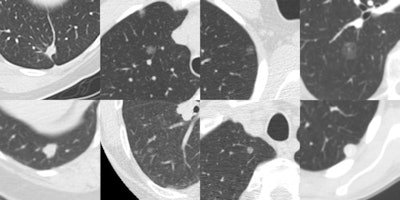

This study used the LIDC/IDRI dataset consisting of 1,018 helical thoracic CT scans collected retrospectively from seven academic centers. These scans were taken on 16 scanner models from four different CT scanner manufacturers. After exclusion of nine cases with inconsistent slice spacing, or missing slices, and 121 CT scans that had a section thickness of 3 mm and higher, 888 CT cases were available for evaluation.

Besides assessing performance of three state-of-the-art nodule CAD systems, an observer's study investigated whether CAD can find additional lesions missed during the extensive LIDC annotation process. This process involved four radiologists independently reviewing all cases in a first (blind) phase, and in a second unblinded phase, each radiologist independently reviewed their marks along with the anonymized marks of their colleagues. Findings were annotated into nodules 3 mm or larger, nodules smaller than 3 mm, or non-nodule (abnormality in the scan not considered a nodule).